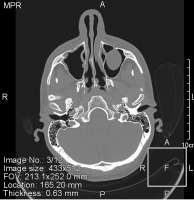

Говорили что кривая, но допустимо. Исправлять ХЗ, есть смысл если боксирую ?

Насчёт зубов, может на снимках видно... Мне об этом ничего не говорили, сам не отдупляю в снимке.

Первый полгода назад до синусита, второй недели 3 назад делал в расцвете синусита, когда нос еле дышал. Второй снимок, это не у меня руки кривые, он сам мутный такой.

На твоих снимках не самая страшная картина, разве что вуаль в левой лобной пазухе, по фотке сложно сказать.

Наиболее иеформативное исследование - КТ придаточных пазух носа, но в твоем случае вроде не нужно. КТ делают, если подозрение на кисты, инорогдные тела или синусит какой-то злой.